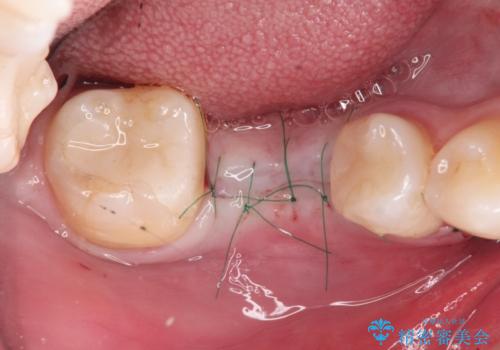

安定し、長く使用できるようなインプラント治療を実践するため、骨の増成をインプラント埋入と同時に行いました。

- 外科手術のため、術後に痛みや腫れ、違和感を伴います